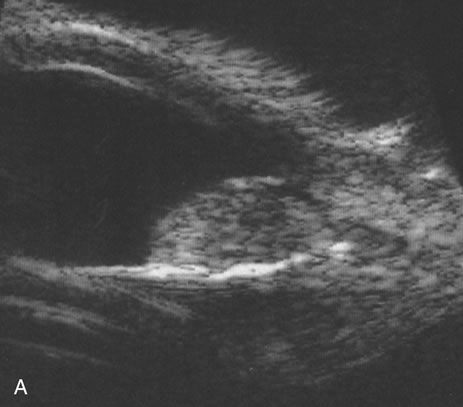

Necrotic melanomas account for approximately 5% of uveal melanomas; in the majority of cases, there is intraocular inflammation accompanying the cataract.7–9Figures 1 and 2 demonstrate a typical case. The patient had a long history of unilateral decreased vision. The eye had become painful 1 month before admission, and he was referred for evaluation of uveitis. Clinically, there was a dense, unilateral cataract with significant intraocular inflammation, which was manifested as a ciliary flush with 2+ cells and flare. Media opacity obscured all fundus detail. An immersion B-scan demonstrated a large intraocular tumor that was most consistent with a uveal melanoma. The eye was removed, and the diagnosis was confirmed histologically.10

Fig. 1. A unilateral media opacity in an adult, requiring that either a foreign body or an intraocular tumor be ruled out. The finding of a large episcleral (“sentinel”) vessel was consistent with either an intraocular tumor or an inflammation. An immersion B-scan helped determine the diagnosis (see Fig. 2).

Fig. 2. Immersion B-scan of the patient in Figure 1 demonstrates a uveal melanoma.